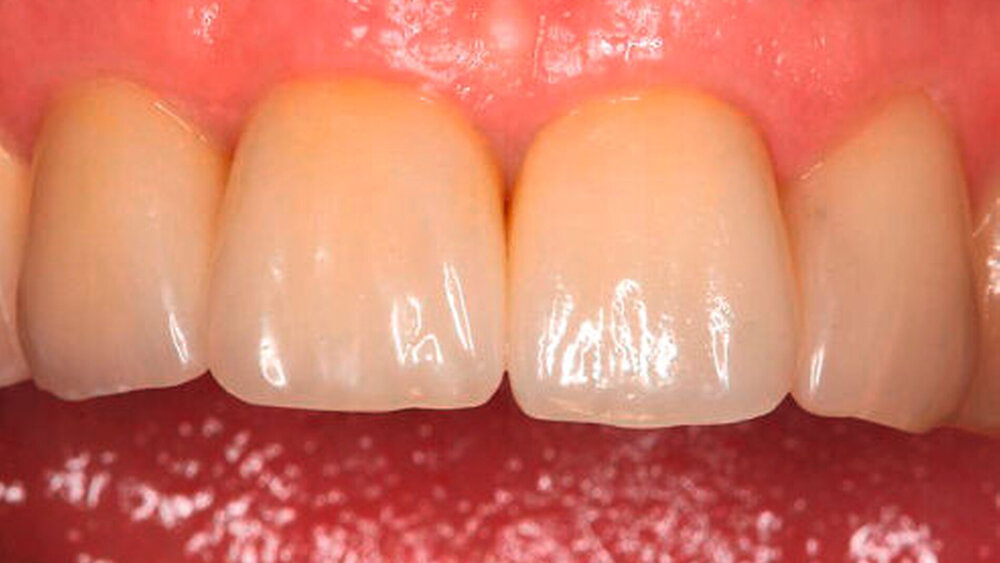

Bei einer jungen zahnlosen Patientin mit schmalem Alveolarkamm wurde klassisch präimplantologisch augmentiert (vestibulärer Knochenblock und BioOss-Anlagerung, Bio- Gide-Membran-Abdeckung) mit vier bis sechs Monaten Einheilzeit. ‧Unglücklicherweise entwickelte sie eine Wunddehiszenz mit ausbleibender Knochenregeneration und Verlust des Augmentats. Eine erneute Augmentation kam für sie wegen der OP-Belastung und einer sich weiter verlängernden Therapiedauer nicht infrage. Als eine mögliche alternative Versorgung stimmte sie der Insertion von drei Profile EV-Implantaten mit abgeschrägter Implantatschulter zu. Die Kontrolluntersuchungen nach zwei und fünf Jahren zeigten eine sehr gute Osseointegration und zudem eine sehr gute stabile periimplantäre Weichgewebssituation ohne zusätzliche peri‧implantäre Weichgewebsver‧dickung, ein Phänomen, so Wagner, das ein typischer Weichgewebevorteil für alle Implantate mit Platform Shift sei, nicht nur für das Profile EV. Als Hauptindikationen für diese anatomischen Implantatformen nannte Wagner

die Sofortimplantation in der Oberkieferfront, die die physiologische Höhendifferenz der Alveole berücksichtigt,